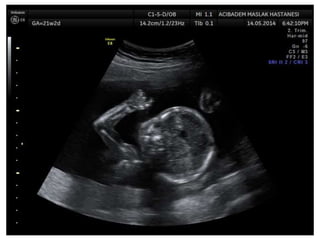

Arthrogryposis

•Multiple congenital joint contractures/ankyloses

involving two or more body areas

•Pena Shokeir phenotype

micrognathia, multiple contractures, camptodactyly

(persistent finger flexion), polyhydramnios

*many are AR

*Lethal due to pulmonary hypoplasia

• Distal arthrogryposis

Subset of non-progressive contractures w/o associated

primary neurologic or muscle disease